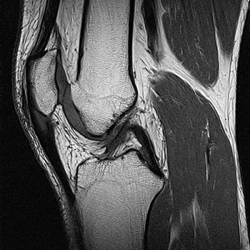

Kernspintomographie

Die radiologische Gemeinschaftspraxis verfügt mit dem 1,5T Hochfeld Cardio – MRT über eines der besten am Markt verfügbaren High- End – Geräte, das nicht nur Ganzkörperuntersuchungen sondern auch Darstellungen des Gefäßsystems über Verschiebetischeinrichtung ermöglicht.

Die Kernspintomographie (übliche Abkürzungen MR, MRT, MRI, NMR, KST) ist eine bildliche Darstellung des Körpers ohne Röntgenstrahlen. Hierbei ist es möglich, sehr dünne (0,7-8mm), bildhafte Schnitte durch den Körper in jeder beliebigen Richtung des Raumes (multiplanar) zu legen, um somit krankhafte Veränderungen auszuschließen oder feststellen zu können.

• Orthopädische Fragestellungen einschließlich MR Arthrographie

Aufgrund der ausgefeilten Methode gibt es unterschiedliche Untersuchungsindikationen - und -Techniken. Um ein optimales Untersuchungsergebnis zu erzielen, mag im Einzelfall ein spezielles Verfahren notwendig sein. Gerne beantworten wir Ihre Fragen.